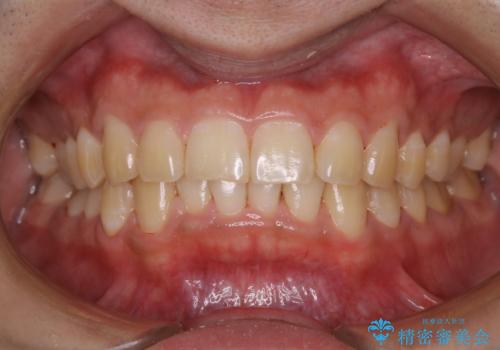

数年ぶりに歯のクリーニング(PMTC)

- しばらく歯科へ行っていなかったため綺麗にクリーニングしたいとのことでした。全体的に汚れが付着していたためPMTC60分コースを行いました。